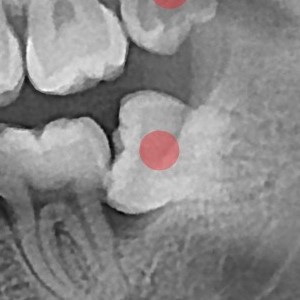

사랑니발치 20대/남성

5e20e086184bc11a2d853605b7813944_1764319844_7796.jpg